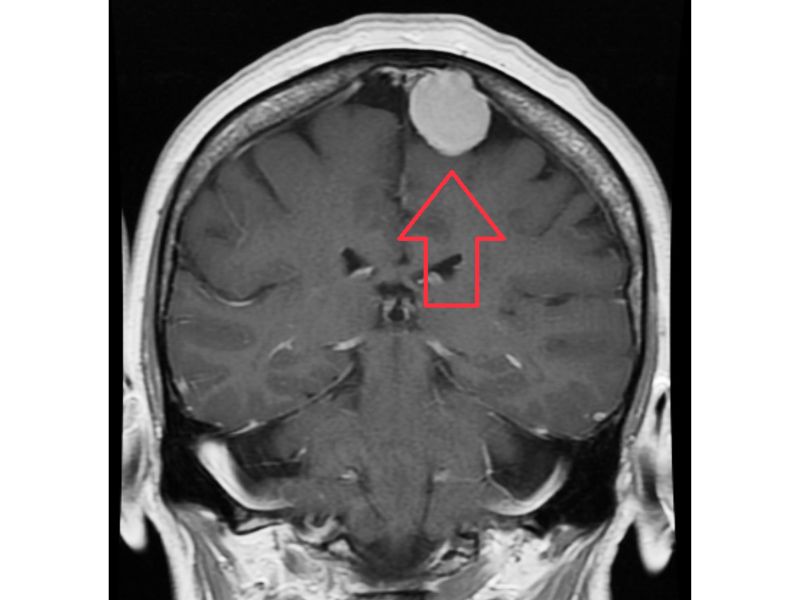

U màng não là một loại khối u nguyên phát của hệ thần kinh trung ương, bắt nguồn từ các tế bào nhung mao màng nhện trong màng não. Đây là dạng u phổ biến nhất của hệ thần kinh trung ương, chiếm khoảng 37,6% tổng số khối u nội sọ và gần 50% các khối u não lành tính. Màng nhện, nơi xuất phát của khối u đóng vai trò quan trọng trong việc bảo vệ não và duy trì hoạt động tối ưu của hệ thần kinh trung ương.

U màng não có thể gặp ở mọi vị trí trong hộp sọ, tuy nhiên các vị trí thường phát hiện u màng não bao gồm đỉnh đầu, hai bên thái dương và đôi khi trong ống sống (u màng cột sống hay u màng tủy).

U màng não là một loại khối u nguyên phát của hệ thần kinh trung ương